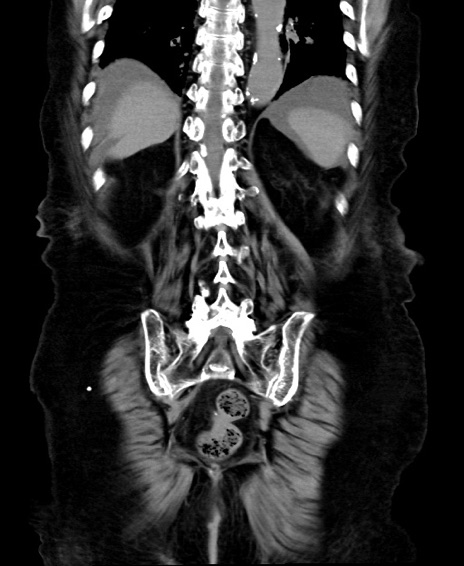

症例40(冠状断像)他院1日前

【症例】90歳代女性

【主訴】腹痛・嘔吐

【現病歴】 食欲低下、嘔吐があり昨日他院受診。肺炎と診断され入院となる。入院後より腹部全体に圧痛あり。胃管留置され経過みていたが、症状持続するため、

当院転院となる。

【既往歴】胸椎圧迫骨折、胆石症

【身体所見】腹部:中央に激痛あり、圧痛あり、反跳痛不明

【データ】WBC 17100、CRP 18.82

冠状断像